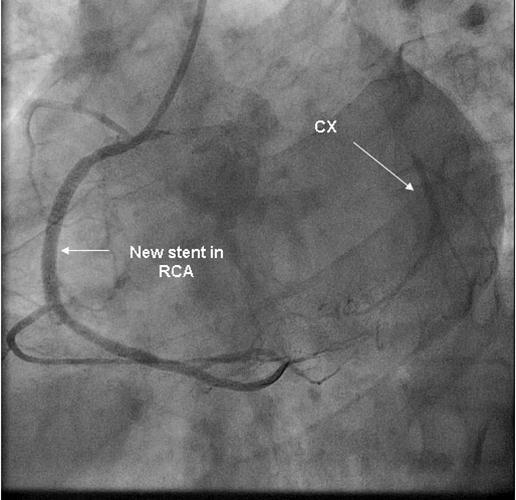

Coronary angiography was again performed. On injections into the left system, collaterals to the distal RCA were demonstrated (figure 1), arising from the left circumflex coronary artery (CX). Injections into the RCA demonstrated tight in-stent restenosis, (figure 2) and a drug eluting stent was successfully implanted. After the angioplasty, injections into the RCA were seen to retrogradely fill the CX (figure 3). The suspicion arose that maybe the left coronary artery had been inadvertently damaged during angiography, so the left coronary was again cannulated and injections performed, demonstrating entirely normal left main and CX arteries. However, the collateral flow that had previously been demonstrated from the CX to the RCA was no longer apparent. On review of the previous angiogram, it was noted that the RCA retrogradely filled the CX despite the original significant stenosis (figure 4). In essence, it became apparent that the bidirectional filling of the RCA from the CX and vice versa was in fact a direct continuity between the vessels and not collaterals, as free flow was noted from the RCA to the CX even when both arteries were completely patent.

Figure 3.New stent in RCA with retrograde filling of CX